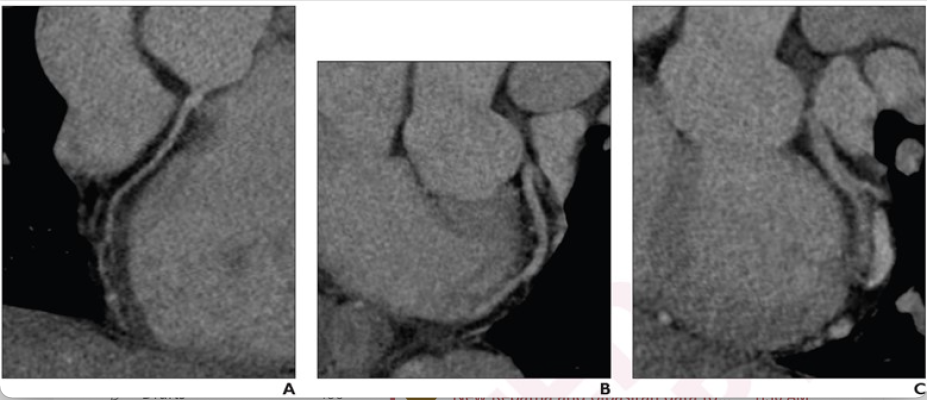

33-year-old, low risk of acute coronary syndrome, presents to off-hour ED with acute chest pain. Patient underwent coronary CTA using 64-detector row SSCT scanner, with heart rate control. Mean heart rate during acquisition was 89 bpm. Curved MPR images of right coronal artery (A), left anterior descending coronary artery (B), and left circumflex coronary artery (C) show poor image quality. Severe motion artifact is present in distal segments of RCA and LCX, and additional artifact from chest wall movement is present in proximal portion of left main coronary artery, leading to nondiagnostic examination. CT completion time was 236 minutes, disposition time was 79 minutes, and ED LOS was 601 minutes. Patient was discharged from ED without cardiology consultation, and did not undergo invasive coronary angiography or revascularization, nor experienced 30-day all-cause mortality or major adverse cardiovascular event